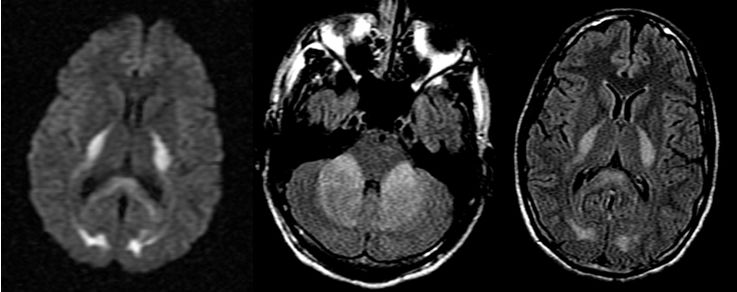

女,36岁,突发意识障碍伴抽搐。

答案:狼疮脑病合并可逆性后部白质脑病综合征(PRES)。补充病史:SLE病史。患者青年女性,有SLE病史,发作性神经系统症状,结合影像学考虑PRES。轻度PRES表现为皮质下或皮质下白质水肿,无实质出血、占位效应、或仅累及脑干或基底节中的一个。中度PRES表现为融合性水肿,从皮质向深部白质延伸,但不延伸至脑室边缘,小脑、脑干或基底节区中有两个轻度受累。重度PRES表现为从皮层到脑室的融合性水肿,或水肿或出血引起中线移位,小脑、脑干或基底节区均受累。

PRES本质上是一种可逆性的血管源性水肿,伴急性神经系统症状,如癫痫发作,脑病,头痛,视觉障碍等。常见原因为:高血压、肾衰竭、使用细胞毒*药性**物、自身免疫性疾病、子痫前期或子痫。约半数PRES患者既往有自身免疫性疾病,如:SLE、血栓性血小板减少性紫癜、甲减、硬皮病、Crohn病、溃疡性结肠炎、类风湿性关节炎、干燥综合征、结节性多动脉炎、肉芽肿性血管炎和视神经血管炎。PRES常由急剧的血压波动或细胞因子对血管壁的直接作用致内皮损伤,引起血脑屏障的破坏,继而引起脑水肿。对称性枕叶皮质下病变要和MELAS鉴别,二者形似神也似。MELAS 的MRI 表现为后部皮层信号改变、脑萎缩、基底节信号改变和钙化、脑白质营养不良。急性期通常会出现 T2 和 FLAIR 高信号,DWI 成像弥散受限。